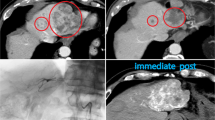

a A waterfall plot showing treatment response for each of the PDX sample (see criterion in Materials and methods). Bars are color coded according to expression level of ABCB1 in the vehicle-treated PDXes, blue = 0–99 normalized reads, yellow = 100–1000 normalized reads, and red = >1000 normalized reads (for normalization method used see Materials and methods). b Quantitative analysis of ABCB1 expression in SK-MEL-2 cells after transduction with an ABCB1-expressing virus, compared with the control virus (±SD) (p < 0.0001), as analyzed with qRT-PCR. c Quantitative analysis of protein expression in the same cells, as b, analyzed with flow cytometry. d Quantitative analysis of activity of p-gp pumps using the p-gp substrate Rhodamine 123, as analyzed using flow cytometry, cells either treated with the p-gp inhibitor Elacridar (1 µM) or DMSO. e SK-MEL-2 cells transduced with ABCB1-expressing virus or control virus, treated with different concentrations of karonudib in combination with 0.1 µM Elacridar or DMSO for 48 h. Cells analyzed using flow cytometry, and the data shown as average of triplicate (±SD). Statistically significant rescue effect was observed when SK-MEL-2ABCB1 cells were treated with 0.5 µM karonudib (adjusted p value 2.6*10−8). f Immunohistochemical staining of ABCB1 in vehicle and karonudib-treated xenografts from the progression group

To address the functional importance of high ABCB1 expression, we transduced the melanoma cell line SK-MEL-2 with either an ABCB1-expressing virus or a control virus. Using quantitative real-time PCR, we observed statistically higher expression of ABCB1 in the ABCB1-transduced cells, compared to the control (p < 0.0001) (Fig. 3b). Furthermore, we verified that the high mRNA expression was translated to protein level, using flow cytometry analysis (Fig. 3c). The pumping activity of p-gp pumps can be followed by flow cytometry analysis of the p-gp substrate Rhodamine 123. Cells with functional pumps cultured in the presence of the substrate will pump out Rhodamine 123 and become negative for the stain over time. Our observation revealed high efficiency of the ABCB1-expressing melanoma cells to pump out Rhodamine 123. This activity could be inhibited with the p-gp pump inhibitor Elacridar (Fig. 3d). When treating the ABCB1-expressing cells with increasing concentration of karonudib, statistically significant less cytotoxic effect was observed for the ABCB1-expressing cells compared with the control cells (adjusted p value < 0.001). This protective effect could be reversed by using the p-gp pump inhibitor Elacridar (Fig. 3e). Finally, to assess if karonudib treatment affects ABCB1 expression or causes selection of ABCB1 high expressing cells, immunohistochemical staining of biopsies from four PDXes with high and one with low expression of ABCB1 mRNA (Fig. 3a) was performed. Only one PDX (M150330) showed somewhat higher expression of ABCB1 after karonudib treatment, suggesting that this is not a common mechanism of acquired resistance (Fig. 1f). Taken together, the data show that high expression of p-gp pumps can make cells less sensitive to karonudib treatment.